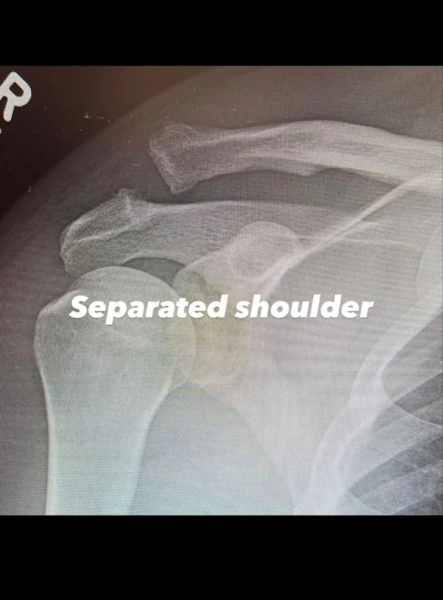

Як з’ясувалося, операція стала необхідною внаслідок дислокації акроміально-ключичного суглоба. Щоб повернути плече у правильне положення, медикам знадобилося виконати хірургічну процедуру.

Окрім того, актор продемонстрував рентгенівські знімки плеча до та після оперативного втручання. Ченнінг Татум не повідомив деталі отримання травми, але запевнив, що сповнений рішучості здолати труднощі та повністю відновитися.